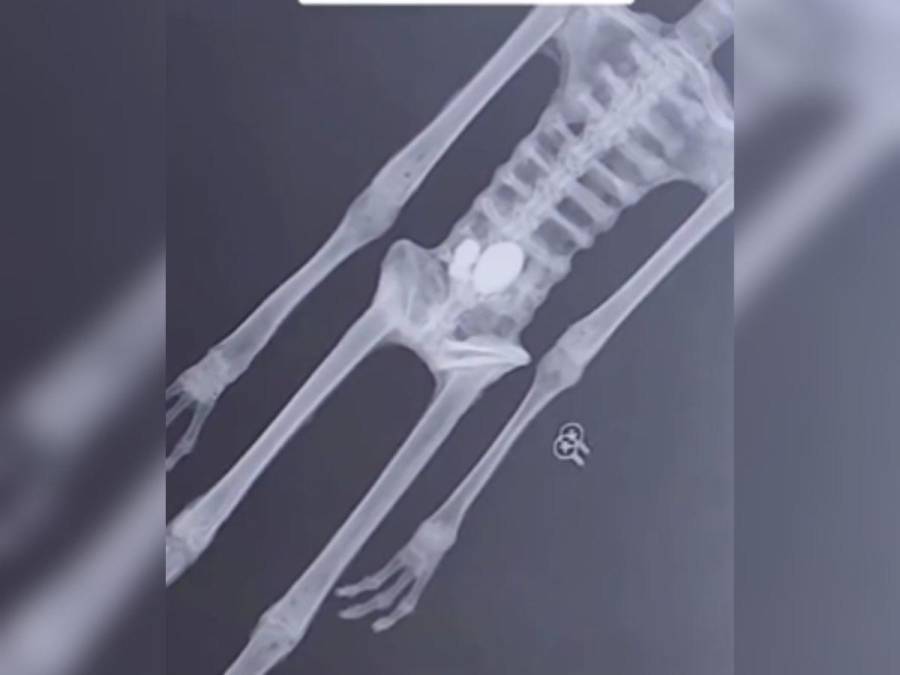

En cuanto a la anatomía, el experto dijo que presentan una estructura humanoide, que consta de cabeza, tronco, abdomen y extremidades, las cuales concluyen en manos y pies tridáctilos, es decir, de tres dedos.

“La estructura ósea de todo el esqueleto, nos muestra una perfecta armonía y concordancia entre las articulaciones, la parte final de cada hueso embona a la perfección con el hueso que le sigue y además se observa el desgaste de estos por el movimiento de la biomecánica, propia del espécimen, siendo huesos muy resistentes pero ligeros, fuertes pero livianos, como los de las aves”, señaló.

Añadió que: “Llegando a las extremidades, podemos señalar que hay una completa armonía y concordancia entre las articulaciones y el desgaste propio de la biomecánica del espécimen, las cuales terminan en manos y pies tridáctilos de cinco falanges, esto les permitiría no ocupar el dedo pulgar como oposición, sino ocupar sus tres dedos en manera de envolvimiento para sujetar las cosas”.

“No cuentan con huesos del carpo y del tarso (huesos en las manos y pies), las falanges son directas a los huesos del brazo y el antebrazo, además de que terminan en una especie de lecho ungueal para la uña”, fueron parte de las apreciaciones. El científico agregó que otro hecho sorprendente es que en la observación microscópica se encontraron huellas digitales, “esto sería imposible de replicar, estas huellas son de particular interés, ya que la mayoría de los especímenes, en este planeta, tienen huellas onduladas o circulares y las huellas de estos especímenes son completamente rectas y lineales, de forma horizontal”.